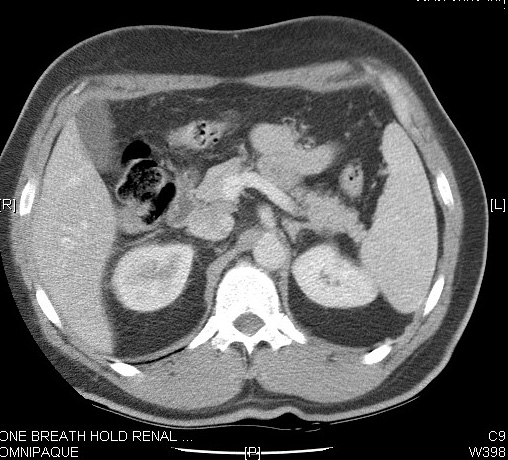

Located in the posterior abdomen, paravertebraly in the retro peritoneum

Measures 9-11 cm in length x 6 cm in Width x 3 cm in AP

The kidney is surrounded by a distinct layer of fascia (Perirenal fascia) that separates the fat surrounding the kidney into the perinephric and paranephric fat. Kidneys lie in a fatty cushion of perinephric fat

Renal cortex

Normal thickness is 2.5 cms